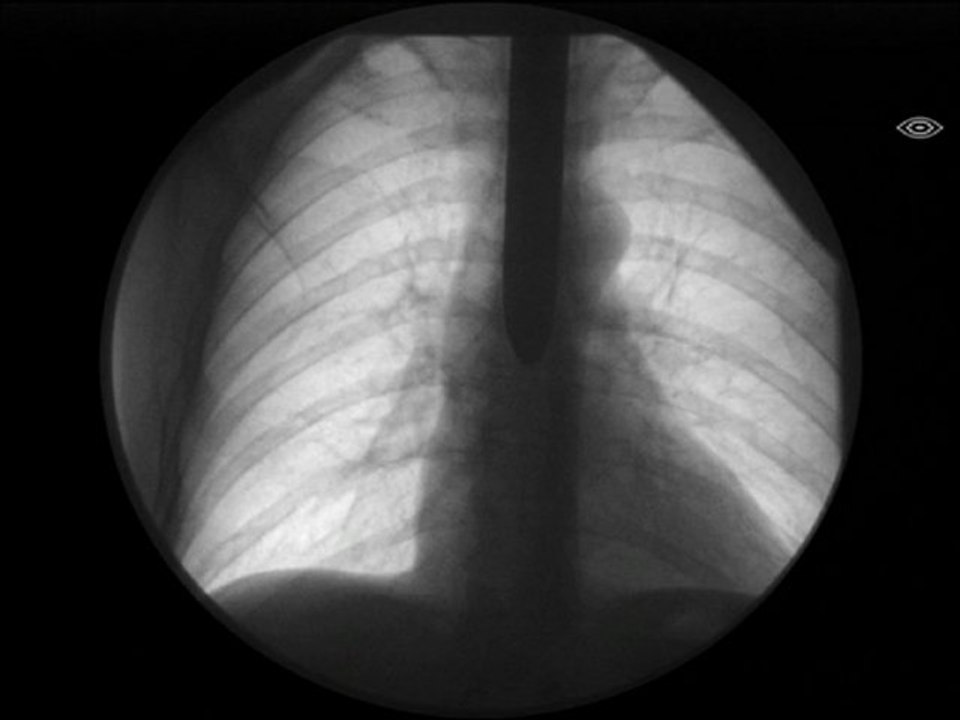

A dangerous magical act where Dr. Gertes swallowed a solid stainless metallic sword ! ! !